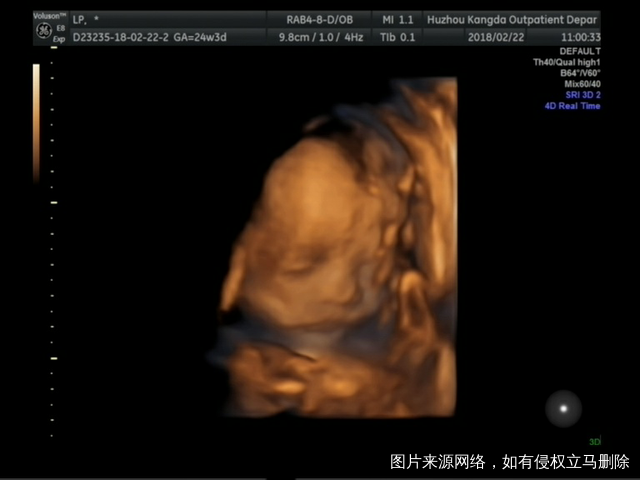

四维宝宝照,希望接下来一切顺利

爸爸过年从部队回来陪了我们二十天,转眼间就回部队了,宝宝是不是好舍不得爸爸啊,妈妈也很想爸爸,四维通过,从上午九点折腾到下午一点,做了三次,终于看全了,宝贝女儿期待你的来临,倒计时还有一百天,加油↖(^ω^)↗